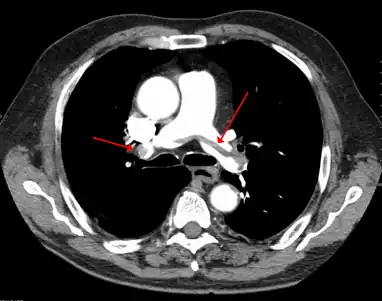

A pulmonary embolism (PE) occurs when a blood clot from a deep vein (a DVT) detaches from a vein (embolizes), travels through the right side of the heart, and becomes lodged as an embolus in a pulmonary artery that supplies deoxygenated blood to the lungs for oxygenation.[28] Up to one-fourth of PE cases are thought to result in sudden death.[12] When not fatal, PE can cause symptoms such as sudden onset shortness of breath or chest pain, coughing up blood (hemoptysis), and fainting (syncope).[29][30] The chest pain can be pleuritic (worsened by deep breaths)[29] and can vary based upon where the embolus is lodged in the lungs. An estimated 30–50% of those with PE have detectable DVT by compression ultrasound.[30]

Thrombolysis is the injection of an enzyme into the veins to dissolve blood clots, and while this treatment has been proven effective against the life-threatening emergency clots of stroke and heart attacks, randomized controlled trials[139][140][141] have not established a net benefit in those with acute proximal DVT.[5][142] Drawbacks of catheter-directed thrombolysis (the preferred method of administering the clot-busting enzyme[5]) include a risk of bleeding, complexity,[l] and the cost of the procedure.[125] Although, while anticoagulation is the preferred treatment for DVT,[125] thrombolysis is a treatment option for those with the severe DVT form of phlegmasia cerula dorens (bottom left image) and in some younger patients with DVT affecting the iliac and common femoral veins.[12] Of note, a variety of contraindications to thrombolysis exist.[125] In 2020, NICE kept their 2012 recommendations that catheter-directed thrombolysis should be considered in those with iliofemoral DVT who have "symptoms lasting less than 14 days, good functional status, a life expectancy of 1 year or more, and a low risk of bleeding."[138]

A mechanical thrombectomy device can remove DVT clots, particularly in acute iliofemoral DVT (DVT of the major veins in the pelvis), but there is limited data on its efficacy. It is usually combined with thrombolysis, and sometimes temporary IVC filters are placed to protect against PE during the procedure.[143] Catheter-directed thrombolysis with thrombectomy[141] against iliofemoral DVT has been associated with a reduction in the severity of post-thrombotic syndrome at an estimated cost-effectiveness ratio of about $138,000[m] per gained QALY.[144][145] Phlegmasia cerulea dolens might be treated with catheter-directed thrombolysis and/or thrombectomy.[19][143]